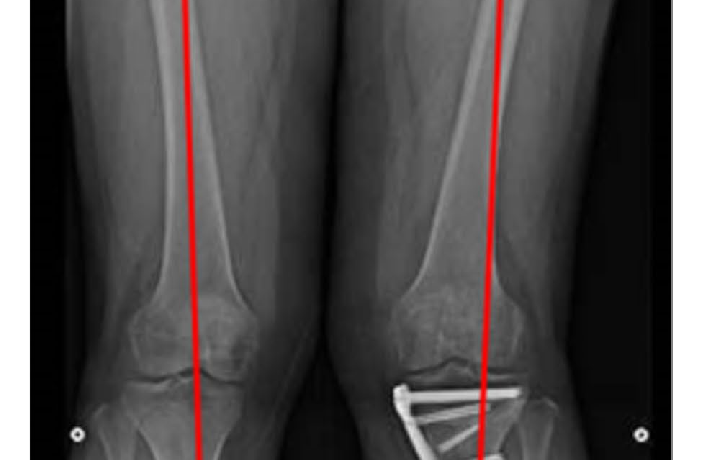

What is ACL Reconstruction? ACL reconstruction is a keyhole (arthroscopic) surgery done to restore stability of the knee after an ACL tear.

The torn ligament is replaced with a tendon graft, commonly taken from the patient’s own hamstring or peroneus tendon. Knee instability or giving-way Sports injuries Associated meniscus or cartilage…